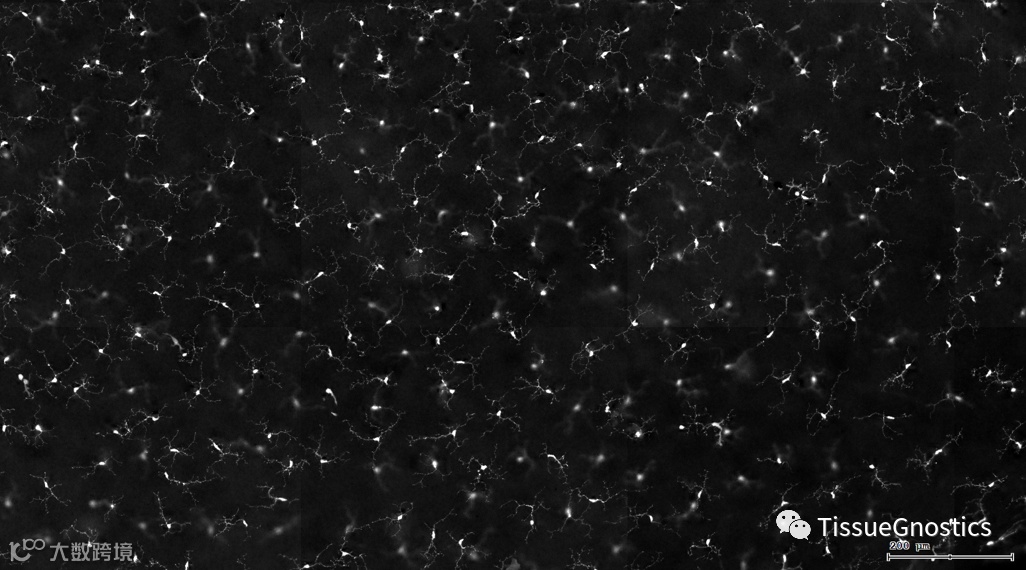

其它中枢神经系统内也有小胶质细胞,在健康的视网膜中,神经元和小胶质细胞之间的交流对维持神经元向大脑发送信号的能力非常重要。

视网膜荧光样本中小胶质细胞胞体、神经纤维识别、血管识别、血管斑点识别、神经元与血管的距离分析。

3. 根据FITC通道识别神经胞体并筛选出有效细胞胞体(细胞核识别算法)。

4. 膜识别FITC染色信号的区域确定神经纤维,并对不同长度神经纤维进行分类。

根据染色强度,染色面积,细胞形态学,利用正反向回溯功能和设门圈选Gating,排除杂质,细胞碎片,黏连细胞(绿色框线标记),获得有效的神经元胞体,(粉色框线标记),并将胞体按照面积分为两类(散点图)。

由于该视网膜样本是标记的小胶质细胞,根据面积将神经胞体分为两类(Small bodycell,Big bodycell),反向回溯Big bodycell中的细胞后,应用Input Gate功能筛选短粗的神经纤维,作为激活态的小胶质细胞。

激活态小胶质细胞识别